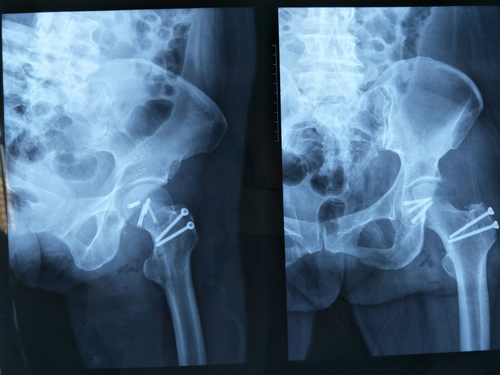

半脱位的比较明显的特征就是髋关节弹性固定于屈曲,内收,内旋位,等等问题的情况出现,那么如果出现髋关节向外面扩展开来,而且患肢出现了短缩,大而粗,突出隆起等情况,那么就意味着实际上髋关节也是属于半脱位状态了,那么这个情况就是需要十分的认真重视,并且到相应的骨科医院进行就诊和治疗,避免因为拖久出现其他问,这样治疗起来,也有其他的麻烦,还是应该早发现早治疗,争取早日康复。